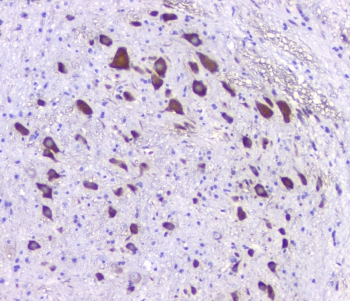

The mammalian HTR2A (5-HT2A receptor) is a subtype of the 5-HT2 receptor that belongs to the serotonin receptor family and is a G protein-coupled receptor (GPCR). This is the main excitatory receptor subtype among the GPCRs for serotonin (5-HT), although 5-HT2A may also have an inhibitory effect on certain areas such as the visual cortex and the orbit frontal cortex. This receptor was given importance first as the target of psychedelic drugs like LSD. Later it came back to prominence because it was also found to be mediating, at least partly, the action of many antipsychotic drugs, especially the atypical ones. 5-HT2A also happens to be a necessary receptor for the spread of the human polyoma virus called JC virus. Sparkes et al. (1991) concluded that the gene is located on 13q14-q21 in man and on chromosome 14 in the mouse.

Amino acids KENKKPLQLILVNTIPALAYKSSQLQMGQKKN of human 5HT2A Receptor were used as the immunogen for the 5HT2AR antibody.